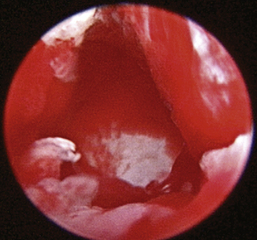

The middle ear consists of an air-filled tympanic cavity, three auditory ossicles, and the tympanic membrane. The tympanic membrane is located at a 45-degree angle in relation to the central axis of the horizontal part of the external ear canal. The tympanic membrane is a semitransparent membrane that separates the external ear canal from the middle ear, is thin in the center and thicker at the periphery, and is divided into two sections, the small upper pars flaccida and the larger lower pars tensa (Figure 20-2). The pars flaccida is the pink, small, loosely attached region forming the upper quadrant of the tympanic membrane that contains small blood vessels. The pars flaccida is usually flat; however, even in the healthy ear one may identify a bulging pars flaccida (Figure 20-3). The exception is the Cavalier King Charles Spaniel, in which a bulging pars flaccida may be indicative of a disease known as primary secretory otitis media (PSOM) (Figure 20-4).

image

Figure 20-2 Normal anatomy of the canine tympanic membrane of the right ear. 1, Pars flaccida; 2, pars tensa; 3, stria mallearis; C, caudal; D, dorsal; R, rostral; V, ventral.

(Courtesy of Dr. Lynette Cole, The Ohio State University, Columbus, Ohio.)

The pars tensa, the thin, tough, gray structure with radiating strands, occupies the remainder of the membrane. The pars tensa is attached to the osseous ring of the external acoustic meatus. The manubrium of the malleus attaches to the medial surface of the tympanic membrane. The outline of the manubrium of the malleus, the stria mallearis, may be visualized when the tympanic membrane is viewed externally. The pars tensa has a concave shape when viewed externally because of the tension applied to the internal surface of the membrane, where the manubrium of the malleus is attached. The point of greatest depression is called the umbo.